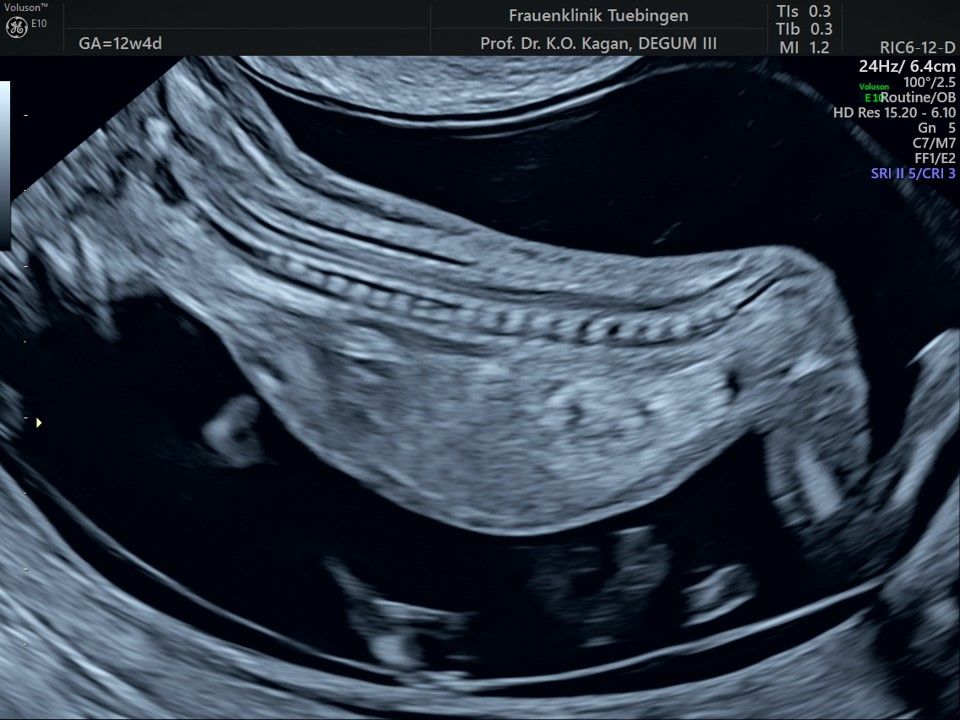

Im Rahmen des Ersttrimester-Screenings untersuchen wir die Organe des Feten mittels Ultraschall. Dabei machen wir auch gerne ein Bild für Sie.

Obwohl der Fet zu diesem Zeitpunkt erst zwischen 5 und 8cm groß ist, lassen sich bereits etwa die Hälfte aller schwerwiegenden Fehlbildungen erkennen bzw. ausschließen. Sollten wir eine Auffälligkeit sehen, werden wir mit Ihnen den Befund und das weitere Vorgehen ausführlich besprechen.

Fetale Anatomie